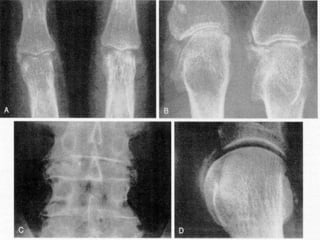

A , Acute pseudogout.  B , Pseudo-osteoarthritis.  C , Pseudo-rheumatoid arthritis with boutonniere deformity.  D , Pseudo-rheumatoid arthritis showing ulnar deviation, interosseous muscle atrophy, and metacarpophalangeal and wrist joint involvement. The patients in  A ,  C , and  D  are siblings.

Radiographic features knee menisci and articular cartilage triangular ligaments of the radiocarpal joint fibrocartilage of the symphysis pubis

A , Acutepseudogout. B , Pseudo-osteoarthritis. C , Pseudo-rheumatoid arthritis with boutonniere deformity. D , Pseudo-rheumatoid arthritis showing ulnar deviation, interosseous muscle atrophy, and metacarpophalangeal and wrist joint involvement. The patients in A , C , and D are siblings.

Radiographic features kneemenisci and articular cartilage triangular ligaments of the radiocarpal joint fibrocartilage of the symphysis pubis